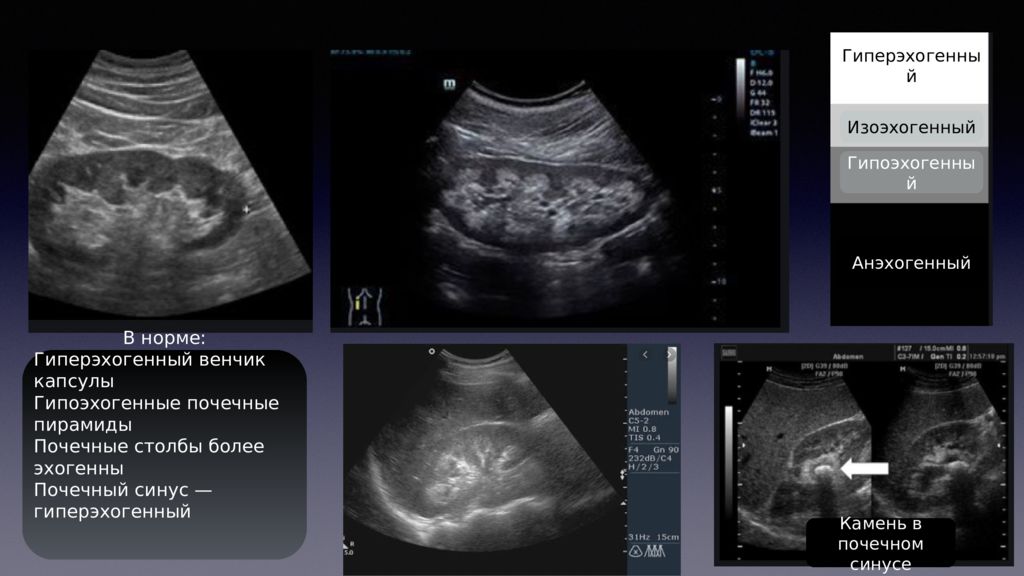

Как выглядит доля Риделя на УЗИ печени